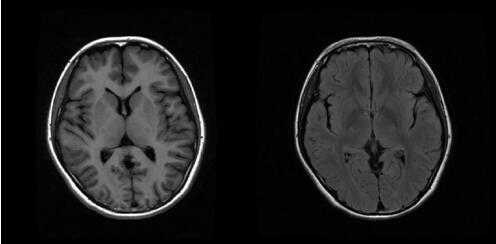

正常人头颅磁共振MR:

患者头颅磁共振MR:

T1加权像壳核、丘脑等处低信号病灶,苍白球呈等信号;T2加权像壳核、丘脑高或稍高信号病灶,但苍白球出现特征性低信号(可能与铜沉积的顺磁作用有关)。